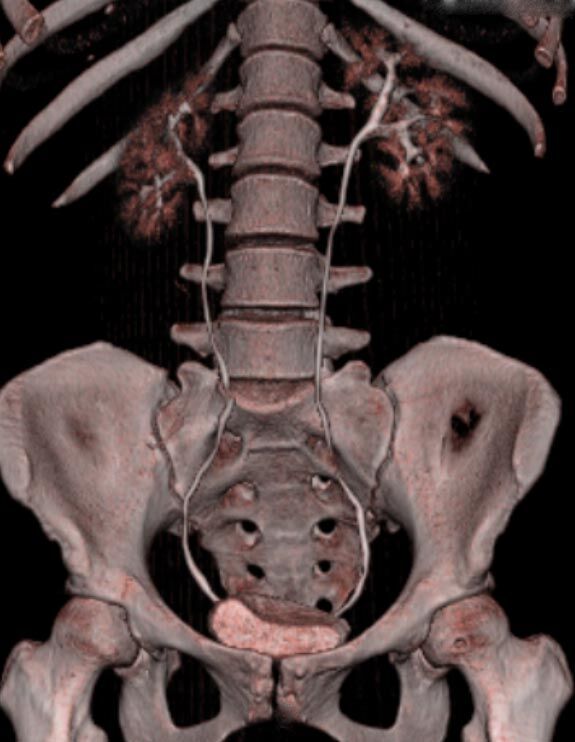

Unser neuer Canon-Computertomograph Aquilion Lightning SP

Seit August 2019 arbeiten wir am Standort Schönefeld mit einem hochmodernen 80-Zeilen-CT der Firma Canon.

Ganz auf Patientensicherheit ausgelegt werden mit diesem CT individuell für jeden Patienten automatisch Strahlendosis und Kontrastmittelmenge reduziert und gleichzeitig bestmöglicher Bildkontrast und eine hohe Detailauflösung erreicht.

Spezielle Software ermöglicht jetzt zum Beispiel:

• verbesserte Bildqualität bei Patienten mit Implantaten (z. Bsp. Hüftendoprothesen)

• besonders hochauflösende, strahlendosissparende Darstellung aller Skelettstrukturen

• mehrdimensionale Darstellung vasculärer Strukturen mit zahlreichen Auswertungstools

Besonders angenehm werden von den Patienten die große Gantryöffnung von 78 cm, die breite Untersuchungsliege und die vergleichsweise geringe Geräuschentwicklung empfunden.